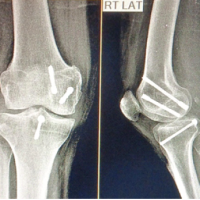

In addition, a Morel-Lavallée lesion was noted near the right kidney and was subsequently debrided with a drain in place. Initial ultrasound imaging of the abdomen revealed minimal free fluid, and the patient was stabilized with hemoglobin levels raised to 10 g/dL. Surgical intervention began with stabilization of the spine through open reduction and internal lumbo-pelvic fixation. The patient was then repositioned to fix the right acetabular fracture using a modified Stoppa approach (Fig. 2).

Figure 2: Post-operative X-ray of lumbopelvic fixation (L5-Iliac); L1 vertebroplasty; Right acetabulum anterior column open reduction internal fixation with 14-hole Recon plate.